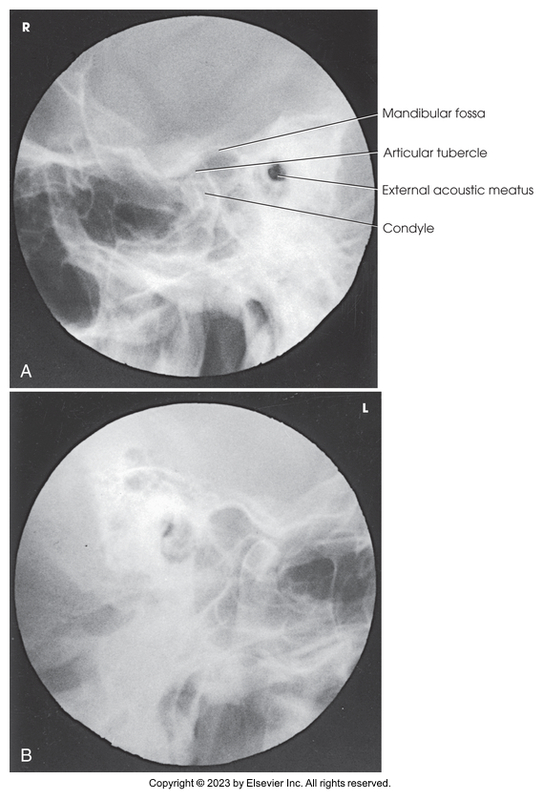

Axiolateral oblique of TMJs - Modified Law Method

Axiolateral oblique of temporomandibular joint - Modified Law method (open and closed)